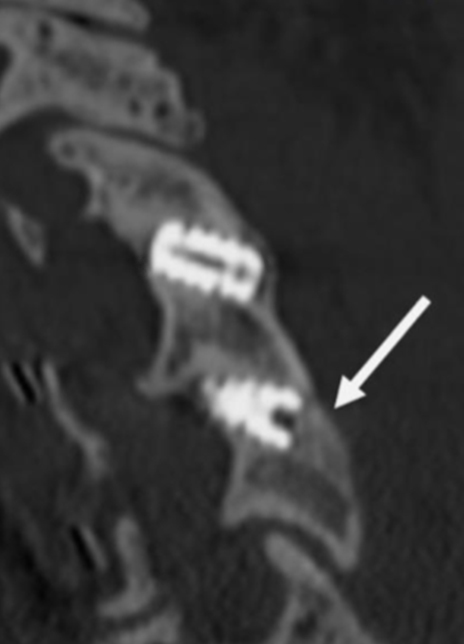

Sagittal CT image showing right anterior/posterior bone bridging.

Sagittal CT image showing posterior bone bridging.

Arrow depicts baseline xray psuedoarthrosis posterior of cage.

CT scan imaging 16 months post op demonstrates osseous continuity posterior of cage.